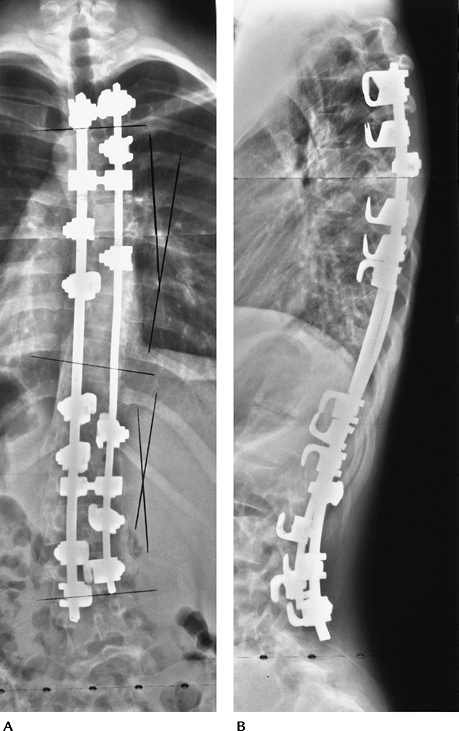

P.77

![]() |

|

FIGURE 3-36 Posterior dislocation. (A) AP radiographs demonstrating prominent paraspinal soft tissue swelling (arrowhead). (B) Lateral radiograph showing posterior dislocation (arrow) in the midthoracic spine. AP (C) and lateral (D) radiographs after Harrington rod instrumentation with sublaminar wire augmentation.